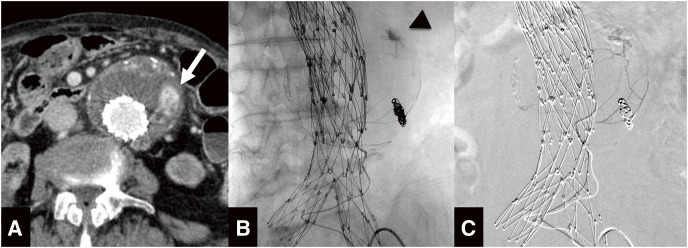

Objectives: The purpose of this study is to evaluate the feasibility and clinical outcomes of vasa vasorum embolization for preventing continuous aneurysmal expansion after endovascular aneurysm repair (EVAR). Methods: We retrospectively reviewed the medical records of patients who underwent vasa vasorum embolization between August 2018 and May 2022. Vasa vasorum embolization was attempted in cases of continuous aneurysmal expansion after EVAR, where the vasa vasorum was identified through catheter angiography. The vasa vasorum was accessed and embolized with a microcatheter. The outcomes of vasa vasorum embolization were evaluated based on technical success, defined as the successful completion of the embolization procedure, and clinical success, defined as the prevention of continuous aneurysmal expansion after the embolization. Results: Seven cases of endoleak with developed vasa vasorum were confirmed by catheter angiography. The mean age was 83.7 years, and the mean aneurysmal diameter was 60.6 mm. Technical success was achieved in 6 cases, while clinical success was not achieved in any of the cases. The mean observation period was 16.5 months, and the mean increase in aneurysmal diameter was 9.7 mm. Conclusions: Although the vasa vasorum embolization is a technically feasible procedure, it is not effective in preventing continuous aneurysmal expansion.

Abstract Image